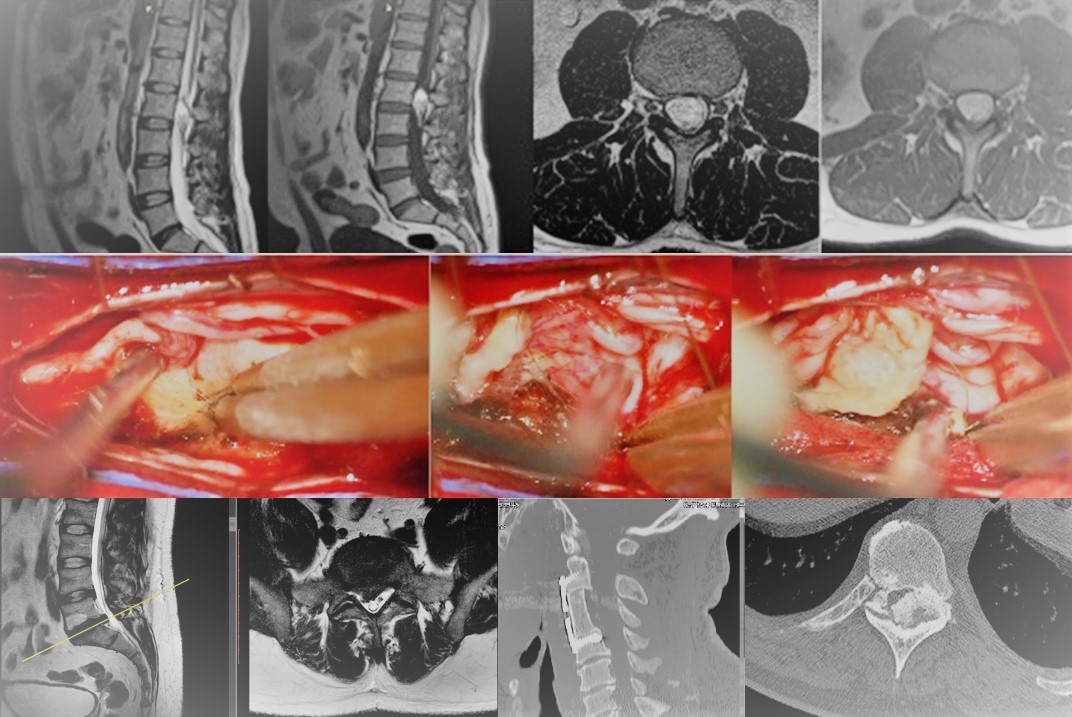

Especialista en el tratamiento de la hernia discal en Almería

Conozca el tratamiento de la hernia discal mediante microcirugía

- Accesos mínimamente invasivos a columna como medio para la preservación de la musculatura paraespinal

- La Microcirugía como herramienta transversal en Cirugía de Columna y Neurocirugía Oncológica